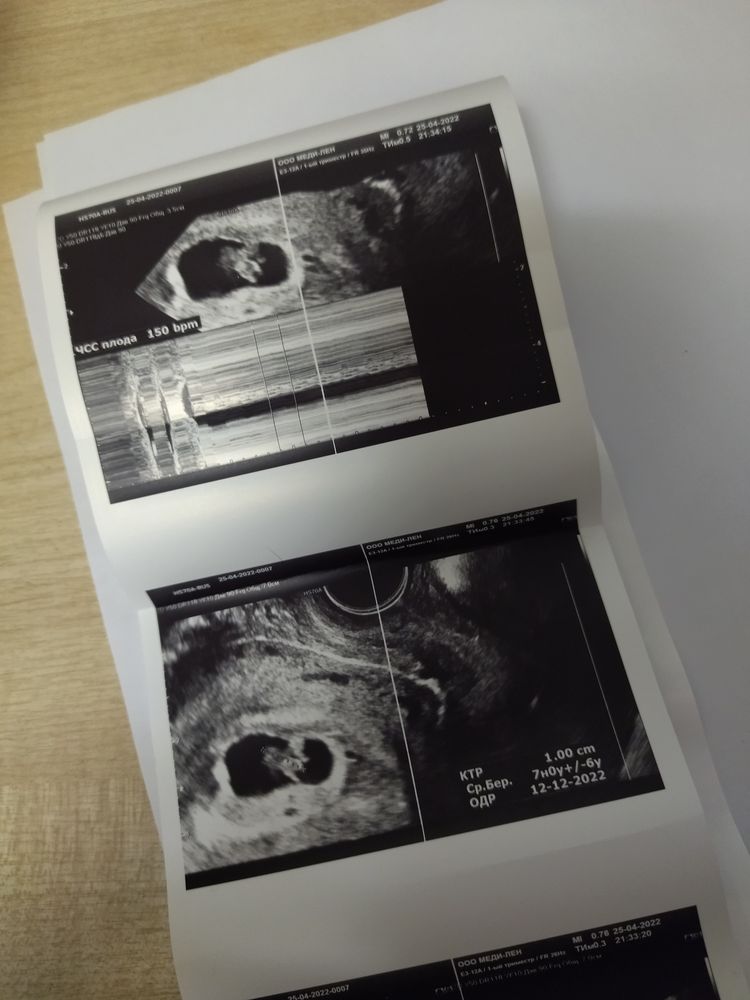

УЗИ 7 нед 2 дня

На УЗИ нашли мою крошку, сердцебиение есть 🙏🙏🙏